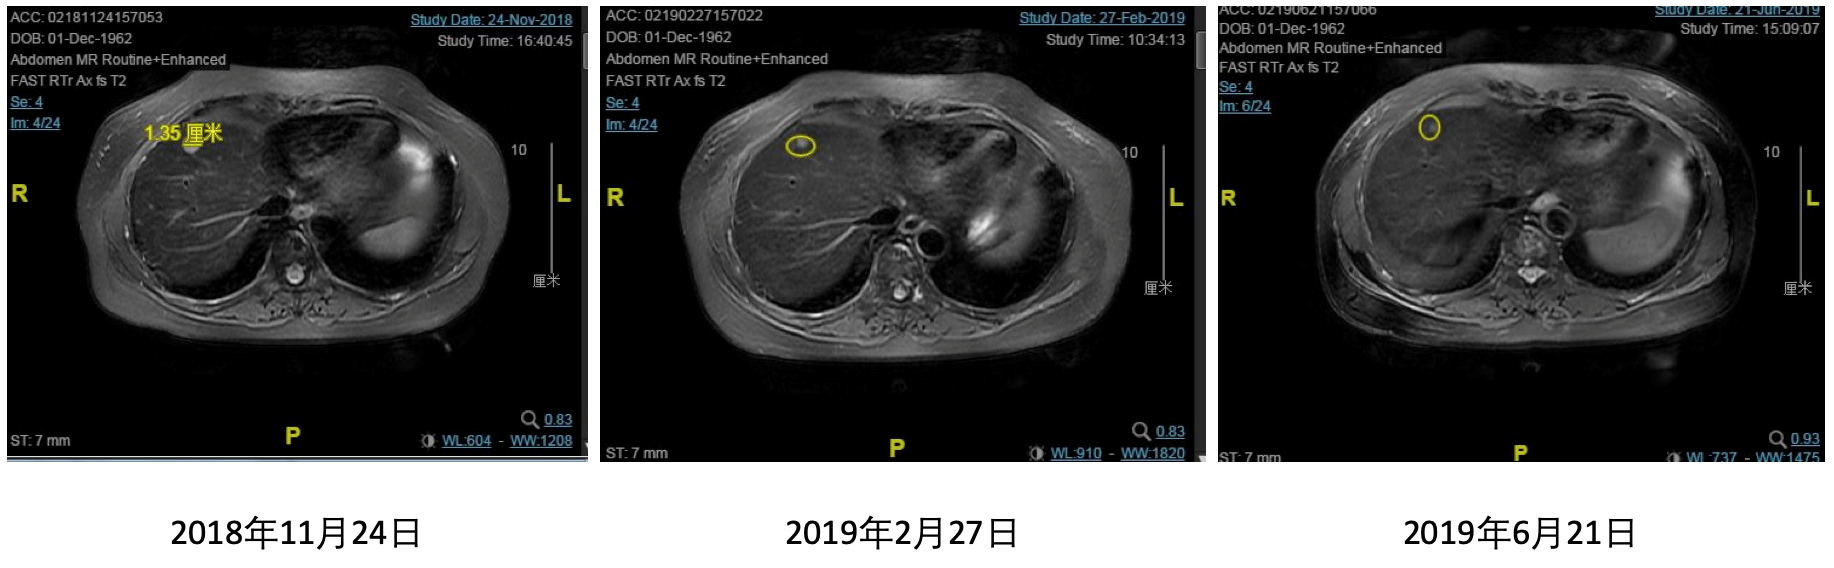

2019年6月21日,患者再次进行随访,腹部MRI(2019年6月21日):肝脏多发转移,较前缩小,腰椎多发转移,较前好转。胸部CT(2019年6月21日):胸部及纵隔淋巴结较前缩小。综合疗效评价为PR。肝脏、腰椎转移病灶前后变化详见图1、2。

图1 治疗后肝脏病灶的变化